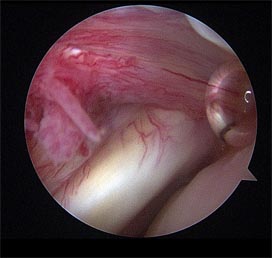

어깨관절의 관절경 수술 모습.

견관절 화농성관절염이 있는 환자의 관절경 사진.

견관절 화농성관절염이 있는 환자의 관절변연절제 후 배농관을 삽입하였음.